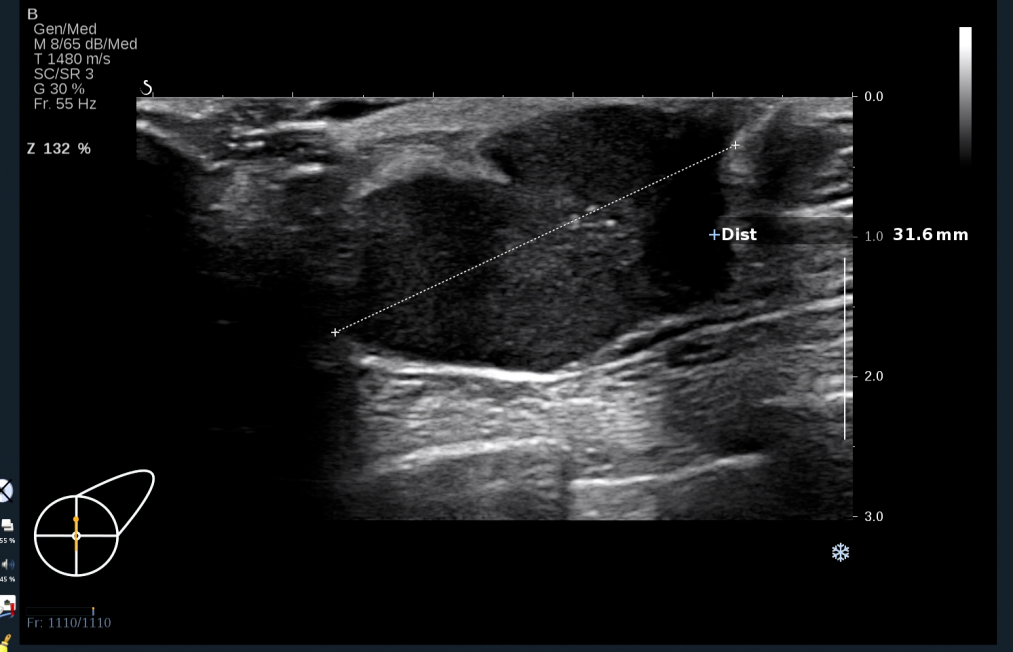

超声可见:左侧乳腺乳头后方可见少量腺体组织回声,其内可见一低回声团,大小约31.6×18.8×17.6mm,形态不规则,周边呈毛刺样,边界欠清,内回声不均匀,可见数个点状强回声。

图2 左乳乳头后方肿块的纵切面声像图表现

图片来源:作者提供